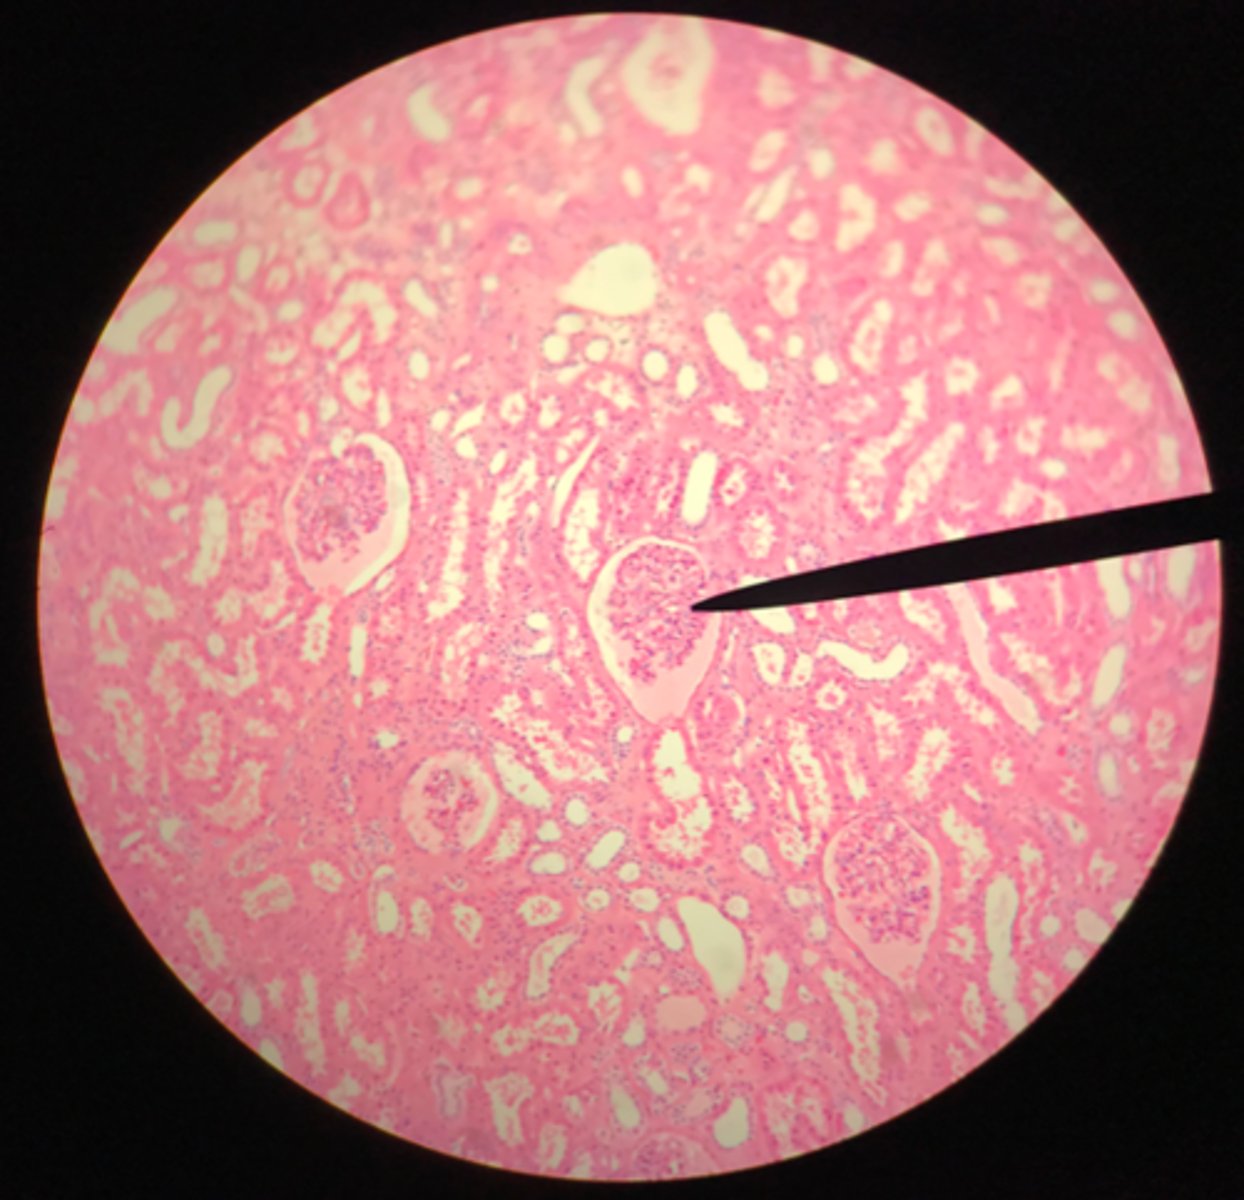

Cortex of the kidney

There are glomerular corpuscles present in the cortex. They are not present in the medulla

What layer of tissue of which organ is depicted on this slide? How can you tell?

Glomerular (Bowman's) capsule (in the cortex)

What structure of the kidney is the blue arrow pointing at?

Glomerulus

What structure of the kidney is the pointer placed on?

Renal tubules (in the cortex)

What structure of the kidney is the blue arrow pointing at?